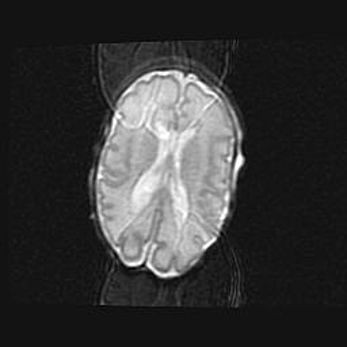

Открытая гидроцефалия.

Возраст: 9 месяцев 12 дней

Вес: 6800 г

Пол: мужской

Окружность головы: 41,5 см

Срок гестации: 28 недель

Гидроцефалия головного мозга у новорожденных имеет характерный признак: опережающий рост окружности головы приводит к визуально хорошо определяемой гидроцефальной форме сильно увеличенного в объёме черепа. Детские неврологи определяют следующие симптомы гидроцефалии у грудничков: выбухающий напряжённый родничок, частое запрокидывание головы, смещение глазных яблок к низу.